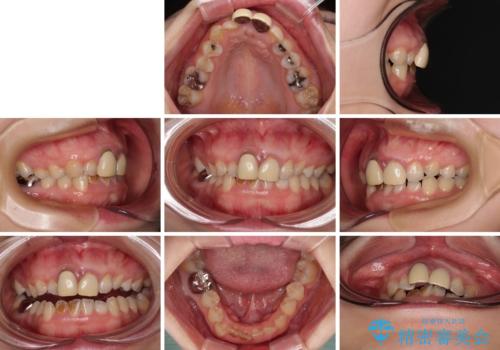

前歯のデコボコをワイヤー矯正で綺麗に 保険診療の前歯クラウンもセラミッククラウンで自然に

- 前歯のデコボコと、着色が著しい保険診療の前歯クラウンを気にして来院された患者様です。

左上の犬歯が埋伏しており、CT画像より萌出は困難と判断されたため、残存している歯にて歯列と咬合を整えることとしました。

マウスピース装着は煩わしいとのことで、表側のワイヤー装置にて矯正治療を行うこととしました。

前歯のクラウンは変色が顕著なため、矯正治療後にオールセラミッククラウンによる補綴治療を行うこととしました。